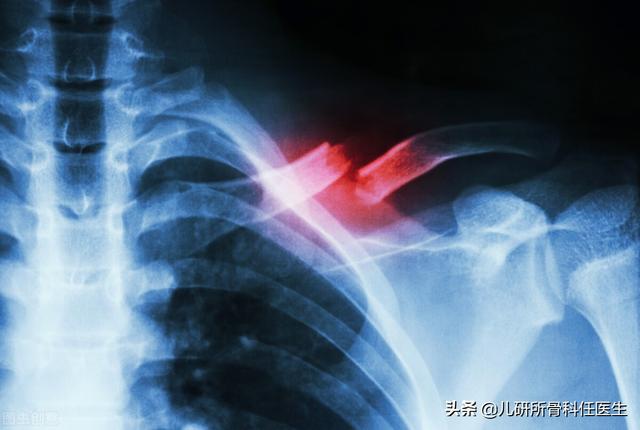

即使出生很长时间,我们也找不到任何问题。偶尔,父母从腋下把宝宝抱起来,或者给宝宝换上外套,按在肩膀上,却发现宝宝莫名其妙地在哭。出生后半个月左右,细心的父母会发现锁骨上凸起的疙瘩。大多数发生在一侧,很少同时发生在两侧。拍照时会发现锁骨骨折,骨折部位会形成更多的骨痂。严重的宝宝会伴有同侧上肢活动度较正常低,表现出神经损伤的症状。

这些锁骨骨折出生的婴儿是真正的天使,带着折断的翅膀来到这个世界。这种骨折,当父母发现时,往往非常紧张和自责。不过听了医生的解释,我很庆幸是锁骨骨折,不是其他问题,因为它的症状比较轻微,大部分不需要治疗。出生后发现的锁骨骨折,可以在宝宝仰卧睡觉时垫在肩膀下面,防止患病的肩膀过度下垂。如果宝宝疼痛明显,可以用毛巾把上臂固定在胸壁上,不用“8”字绷带。得益于新生儿强大的生长动力,10-14天疼痛消失,骨折临床愈合。如果宝宝非常不幸,锁骨骨折伴有臂丛神经损伤,那么就要抓紧时间去专业的小儿骨科或手外科门诊就诊。